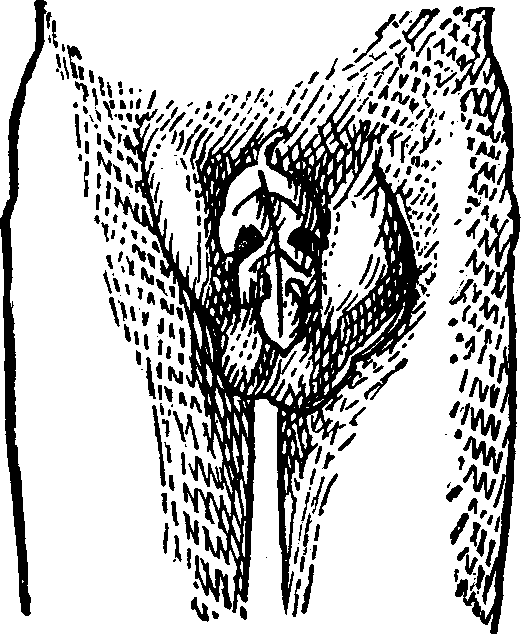

Fig. 1. A. Human

Spermatozoön magnified about 3,800 diameters. B. Vertical and

lateral views of spermatozoa of man. C, D, E, F. Development of

spermatozoa within the vesicles of evolution. G. Cell of the sponge

resembling a spermatozoön. H. Vesicles of evolution from the

seminal fluid of the dog in the parent cell I. Single vesicles of

different sizes. J. Human spermatozoön forming in its cell.

K. Rupture of the cell and escape of the spermatozoön.